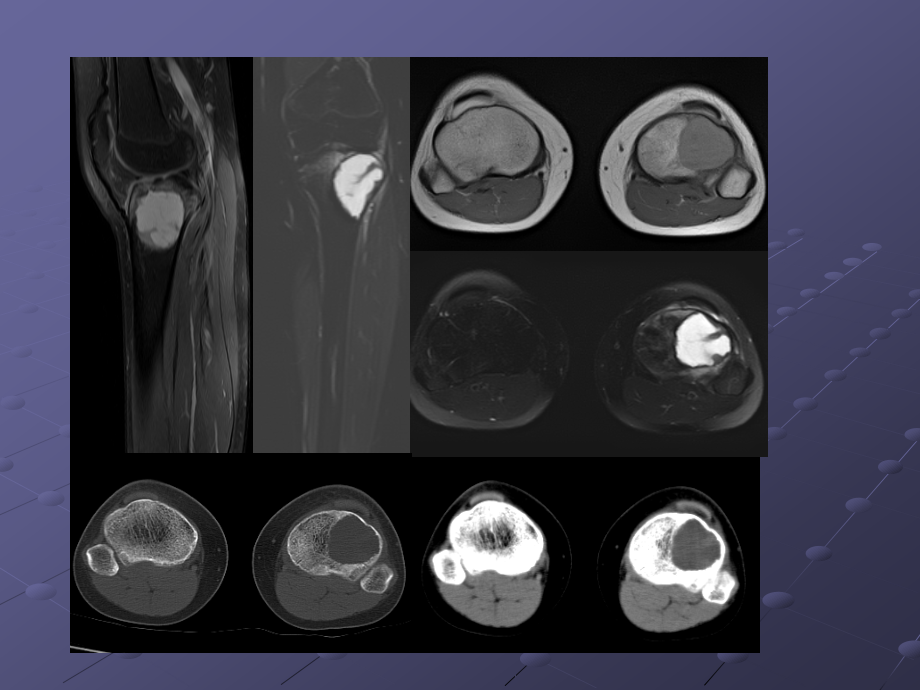

,*,单击此处编辑母版文本样式,第二级,第三级,第四级,第五级,单击此处编辑母版标题样式,15岁,女,01142857,摔伤致左膝痛2-3月,胫骨软骨母,12岁,男,,软骨母细胞瘤的影像诊断,福建医科大学附属第一医院影像科-李玉萍,2015.07.10,软骨母细胞瘤认识发展史,1923年Ewing-钙化的巨细胞瘤。,1927 年 Kolodny-含有软骨的巨细胞瘤。,1931 年 Codman-骨骺软骨源性巨细胞瘤。,1942年 Jaffe和Lichtenstein-成软骨细胞瘤或软骨母细胞瘤(CB Chondroblastoma)。,临床表现,90%的CB患者发病年龄为5 25岁。,临床症状缺乏特异性,以疼痛最常见。30%患者可表现为类似滑膜炎的关节症状。,少数CB具有侵袭性行为,极少数病例甚至有肺转移。,起源及病理,CB的起源存在一定争议。目前多认为起源于软骨细胞的前体,起源于青少年长管状骨骨端和骨骺。,镜检成分为软骨母细胞、基质及多核巨细胞。,单核软骨母细胞免疫酶标记S一100蛋白阳性。,影像表现1,部位:多发生于长骨骨骺或骨突部、中心或稍偏心,极少数病灶可突破骨端进入关节。发病部位以股骨(33%)、肱骨(20%)和胫骨(18%)等长管状骨最常见,近一半发生于膝关节周围,少数可位于手足等不规则骨。,境界:CB多呈境界清楚的溶骨样骨质破坏,长管状骨的骨质破坏多呈圆形,CB境界清楚,多数可见明显硬化边,少数伴有不太宽的硬化带,一方面与肿瘤缓慢生长,刺激邻近成骨细胞有关,也可能为肿瘤边缘钙化所致。极少数发展较快的肿瘤缺乏硬化带或硬化边缘。硬化边的存在对于鉴别诊断很有价值,因为绝大多数骨巨细胞瘤缺乏硬化边,外形:CB内软骨成分常形成软骨小叶状改变,病灶边缘常因此而呈结节状突起;CB瘤骨界面呈扇贝状或花边状,病理基础反映软骨小叶对正常骨结构的挤压。,影像表现2,钙化:,25%50%的CB病灶内部可见钙化,位于软骨小叶间隔的钙化呈直径1 2cm的环状、弓状,具有定性诊断价值;位于小叶内的钙化呈斑点或雀斑状,无序排列,无诊断特异性。,骨膜反应、软组织反应:伴随炎症反应。,30%50%的CB引起骨膜炎,导致骨膜增生,10%增生范围广泛、致密、粗厚,成层并与骨干平行。具有鉴别诊断价值。30%的CB有关节腔积液。CT和MRI上相对常见,X线平片则少见。,CASE1:男,13岁,左侧小腿疼痛半年,冻后及冻余石蜡报告:,(左胫骨上段病变)软骨母细胞瘤伴骨化。,CASE2:男,18岁,右膝发热3个月。右胫骨上段软骨母细胞瘤。S-100(+)。,CASE3:,20岁,男。,肱骨上段软骨母细胞瘤,CASE4:男,38岁,左髋部疼痛1年,左股骨头软骨母细胞瘤,CASE4:男,29岁,右大腿酸痛2年余,病理:符合软骨母细胞瘤,伴动脉瘤样骨囊肿。S-100(+),鉴别诊断-,骨巨细瘤,左胫骨骨巨细胞瘤,15岁,女,01142857,摔伤致左膝痛2-3月,胫骨软骨母,12岁,男,,软骨母细胞瘤。,骨巨细胞瘤:年龄、偏侧,体积较大,密度较低,分隔嵴突、硬化边不清,周围组织炎症反应较轻,,软骨母细胞瘤:偏中心,较小,无分隔、内见弧形钙化、密度较高,可有硬化边、硬化带,周围炎症反应较明显。,鉴别诊断-,内生软骨瘤,女,3岁,鉴别诊断-,骨结核,女,3岁,左胫骨结核,鉴别诊断-,动脉瘤样骨囊肿,典型软骨母细胞瘤影像诊断,5-25岁,长骨骨骺、骨突、可跨越骨骺,溶骨性破坏,硬化边可见,内可有弧形钙化,部分周围伴炎症改变,谢谢大家,